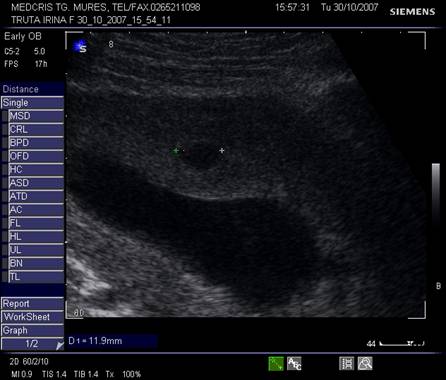

Fig. nr. 82 Ou clar la ecografia transvaginala